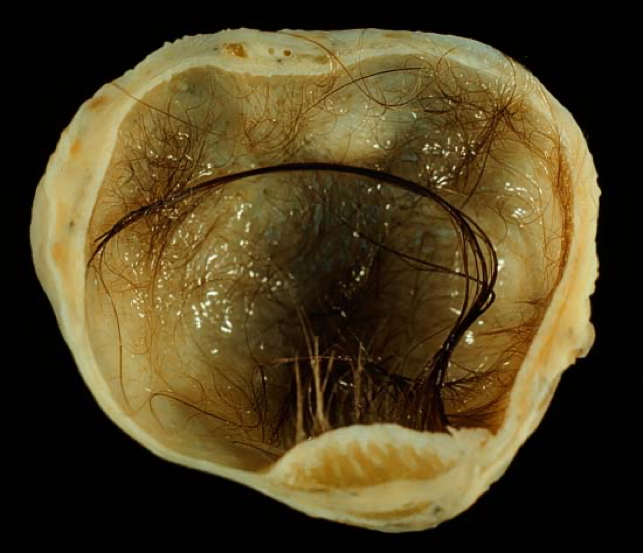

3. Dermoid Cyst (Teratoma)

Morphology

- Macro:

- May contain hair, teeth, skin, brain, fat, etc.

- Micro:

- Mature tissues from multiple germ layers

- Encapsulated